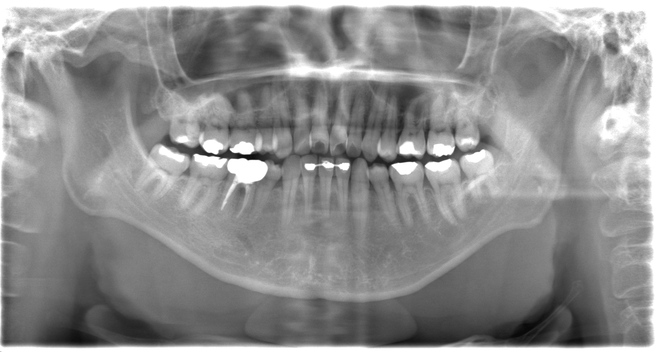

Case02下顎左右6番インプラント(マウスピース矯正を併用)

| 治療期間 | 6ヶ月 |

|---|---|

| 治療費 | インプラント2本1,100,000円 |

| 年齢・性別 | 20代女性 |

| リスクと副作用 | 腫れ、痛み、感染、神経損傷、将来的な脱落 |

| 備考 | 20代女性です。インプラント希望で来院されました。 他院でインプラントを入れるスペースがなく両方の歯を削る必要があると言われ、抵抗があるとのことでセカンドオピニオンで当院に来院されました。 赤坂さくら歯科クリニックオリジナルのインハウスアイライナーのサクライナー矯正で、隙間を閉じた上で一切削らずにインプラントを行いました。 患者様は隙間にものが挟まるストレスからも解放され、とても喜んでらっしゃいました。使用したインプラントはノーベルバイオケア社のインプラントになります。 大臼歯であっても細いインプラントを隙間を矯正などで調整しながら入れることが可能です。 |